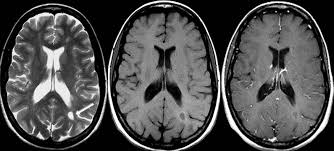

Déficit de atención con hiperactividad: hallazgos en neuroimágenes

23 febrero 2017

La resonancia magnética muestra reducción del volumen de diversas estructuras cerebrales en niños con la afección, pero no en los pacientes adultos. Podría interpretarse como un retraso en la maduración cerebral. The Lancet Psychiatry, 15 de febrero de 2017